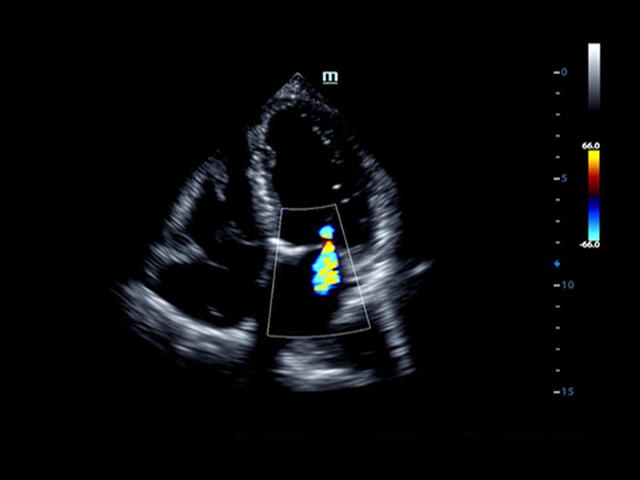

• LVO - опция проведения исследования левого желудочка сердца с применением контрастных веществ;

• LVO - опция проведения исследования левого желудочка с применением контрастных веществ

• Cardiac package - предустановленные параметры, аннотации, маркеры, программы измерений для кардиологии